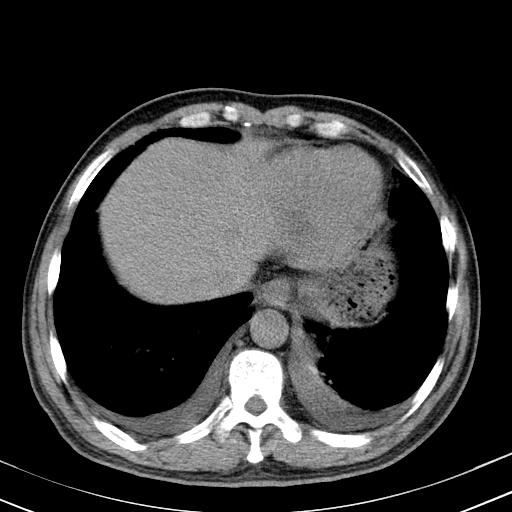

以下是引用zjzjr在2010-3-21 17:39:00的发言:[br]右下中心型肺癌并阻塞性肺炎/不张,纵膈淋巴结肿大,右侧大量胸腔积液,左侧少量胸腔积液

以下是引用zxl51642在2010-3-21 17:06:00的发言:[br]右下中心型肺癌并阻塞性肺炎/不张,纵膈淋巴结肿大,右侧大量胸腔积液,左侧少量胸腔积液,少量腹水。建议纤维支气管镜进一步检查。